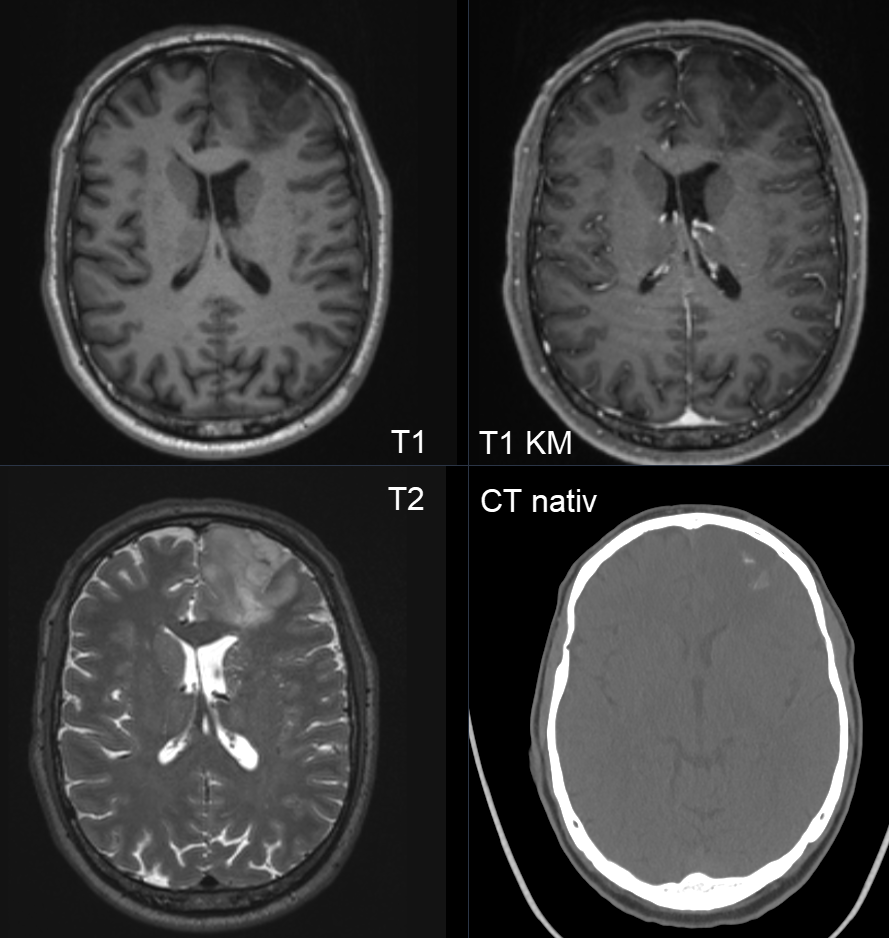

In 90% können bei Oligodendrogliome in einer CT-Untersuchung Kalzifizierungen im Tumor gesehen werden6. Im MRI zeigt sich ein Oligodendrogliom im Regelfall hypointens in der T1 Sequenz und hyperintens in der T2 Sequenz. Eine Kontrastmittelaufnahme besteht in weniger als 20% der Fälle7.